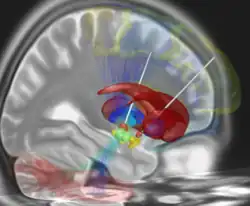

Sample Lead-DBS session. | |

Lead-DBS is an open-source toolbox for reconstructions and modeling of Deep Brain Stimulation electrodes based on pre- and postoperative MRI & CT imaging.